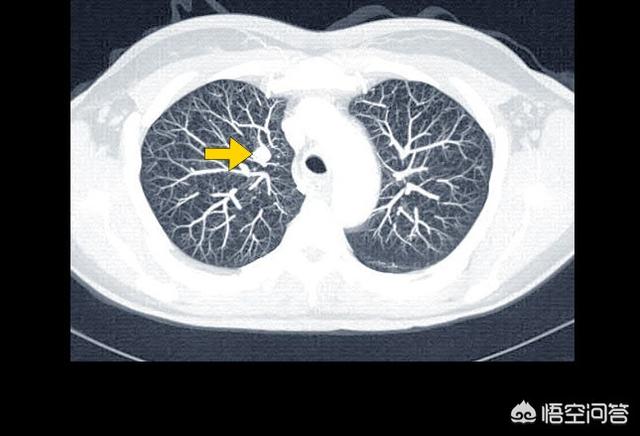

(1) Décédé d'une insuffisance respiratoire

Nous avons besoin des deux poumons pour respirer, et si les poumons sont pleins de tumeurs, ils perdent leur capacité à respirer, et le cancer peut également bloquer les voies respiratoires, et il y a aussi du liquide pleural, dont une grande quantité comprime les poumons et provoque des difficultés respiratoires. Si les poumons ne peuvent pas fonctionner, il n'y aura bientôt plus assez d'oxygène et les organes du corps entier seront privés de sang et d'oxygène et finiront par mourir.